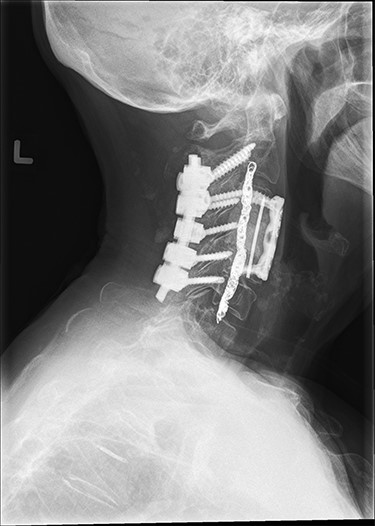

Approximately 24 hours prior to spine surgery, the patient had undergone an interventional radiology procedure to embolize the left vertebral artery. As part of the procedure, an Angio-Seal device was placed in the femoral artery for closure. The next day, stage one of the spine surgery consisted of a posterior C2–C6 (Fig. 3) and a T7–T9 decompression and instrumented fusion while the patient was in the prone position. After the completion of stage one, the patient was moved to a supine position using a Jackson table. During stage two, the patient underwent an anterior C3–C5 (Fig. 3) instrumented fusion with a C4 vertebrectomy.